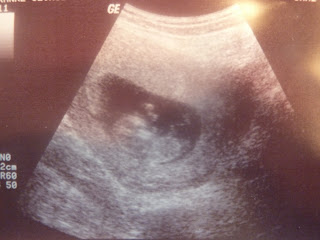

So I definitely have a lot of catching up to do...I have been a slacker when it comes to blogging. I am now 8 months pregnant about seven weeks left and starting to count down. They say that every pregnancy is completely different and I would for sure say that this one has been compared to Mylee. First trimester I was really sick, very tired, and started showing a lot faster. I quickly realized that because I had Mylee plus working at nights and on weekends my energy was shoot. After about 17 weeks definitely started feeling better and had more energy. We were really excited to find out what we were having from the beginning I would say both Jesse and I kept thinking a boy and Mylee always told me it was going to be a boy, the morning we went to find out I asked Mylee what if the Doctor tells us its a girl? She said no she will tell you its a boy, and she was right. We are really excited to have a little boy although its a little weird to think about because i am so used to everything being all girl. Jesse was super excited and couldn't wait to start texting and calling everyone to let them know.

From our twenty week ultrasound appointment we got some worrying news, they had told us they found a hole in the baby's heart which could mean a couple of things if it was small enough it would possibly be able to mend on its own or if it was big enough the baby would have to have open heart surgery as soon as he was born to fix it. So needless to say it was very stressful, we had to go about 5 weeks later to primary children to have a fetal echo done to determine exactly how big the hole was. Very nervous we went in and left with a extremely grateful hearts because everything came back normal, there was no hole and everything looked great. With that under our wing we then found out that the baby only has one kidney and I have only a two vessel umbilical cord instead of a three. Which the vessels are what provides nutrition to the baby. So I have and have had to go in to a specialist every four weeks for an ultrasound where they do all his measurements to make sure he is growing and getting what he needs as well as they monitor the one kidney that he has. Many people live with just one kidney as long as the one they have is healthy and normal so they have been keeping track of the one he has. Once he is born we will have to see a urologist to do ultrasounds on the baby to make sure the one he has is good. So far the baby as been measuring right on track which is been great news meaning that hopefully he is getting what he needs. Although this has been very stressful, it has definitely made me realize the importance of prayer and priesthood blessings and that i need to rely more on these things.

We are anxious to meet our little guy and pray he is healthy and have faith that things will all be okay.